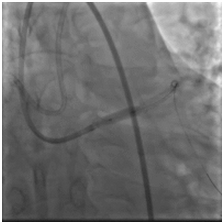

取0.014" Runthrough NS导丝通过病变送入高位钝缘支远端(图4),送入Atlantis SR血管内超声导管至左主干远段,未见明确前降支开口影像,0.014" Sion导丝未能通过前降支近段支架内闭塞病变处,换用0.014" ConquestPro导丝成功通过前降支近段支架内闭塞病变送至前降支中段(图5、6),换入0.014" Sion导丝至前降支远端,Sprinter Legend 2.5×15 mm球囊锚定导丝后,再以该球囊成功通过闭塞病变,反复以10~12 atm×5 s扩张(图7)。复查造影显示前降支恢复TIMI 3级血流,前降支近段处残余狭窄50%,中段局限性狭窄70%(图8)。Sprinter Legend 2.5×15 mm球囊以6 atm×8 s扩张前降支中段病变后,送入IVUS导管至前降支中段连续自动回撤示前降支中段心肌桥征象,近段弥漫性纤维斑块形成。植入Buma 3.5×25 mm雷帕霉素药物支架以10 atm×8 s扩张释放(图9),稍前送该支架球囊至两支架交界处以10 atm×8 s再次扩张塑形。行IVUS检查左主干内支架贴壁不良。取Quantum 4.5×12 mm高压球囊至左主干支架内以14~20 atm×8 s扩张塑形(图11),复查造影示支架扩张满意,残余狭窄<30%,血流TIMI 3级,回旋支血流未受影响(图12)。复查血管内超声示支架扩张满意,贴壁良好,支架两端无夹层征象。

图5、6